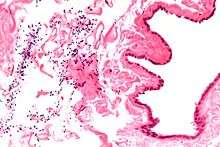

Micrograph of a spermatocele. The characteristic sperm are present (black dots - left of image). H&E stain.